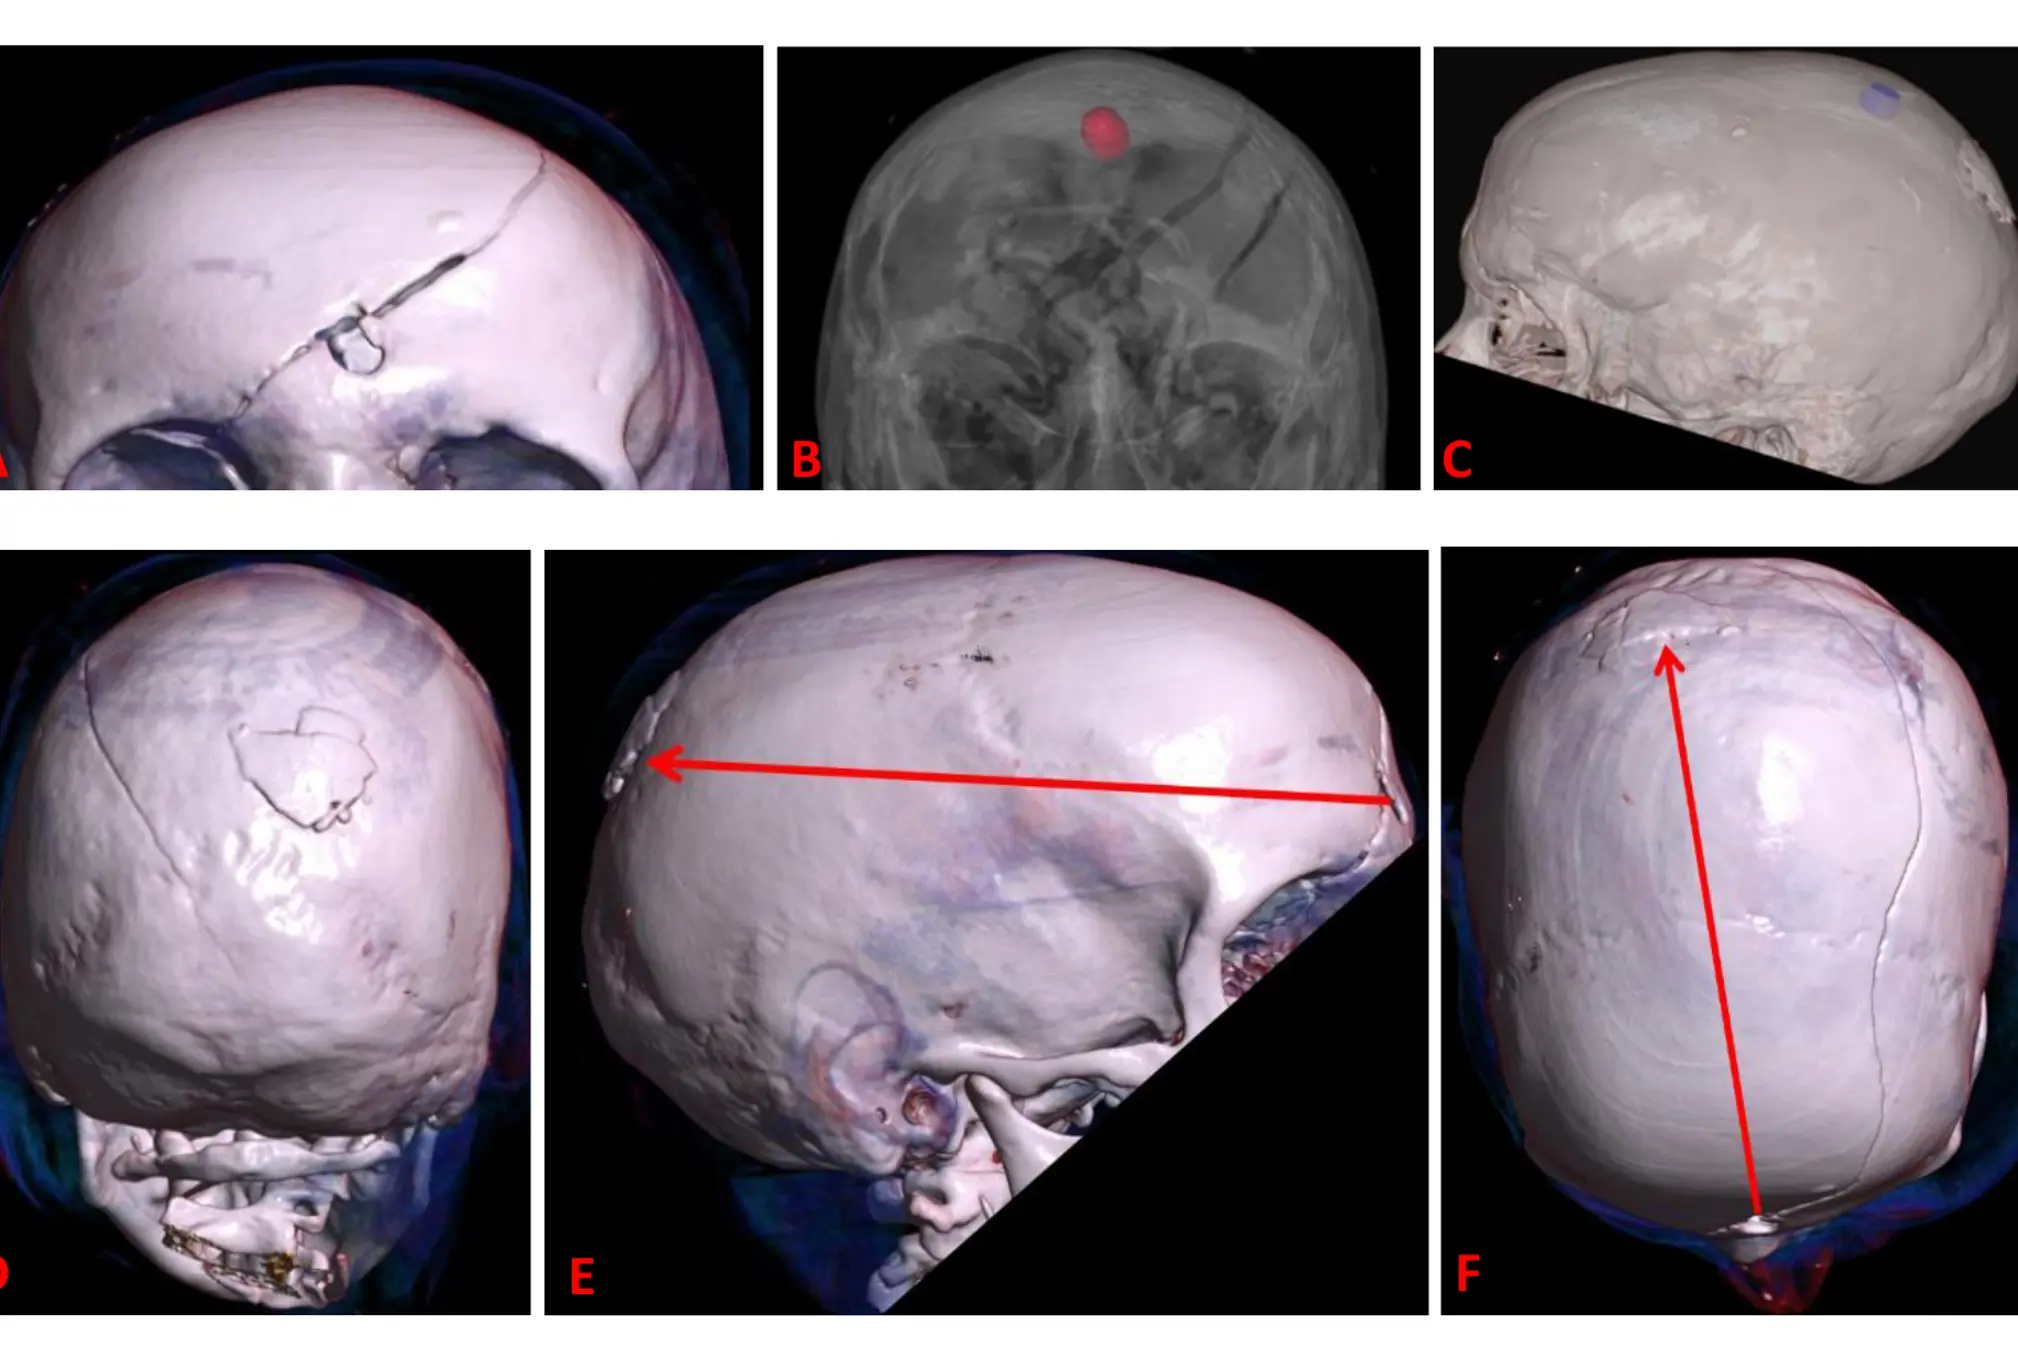

Fig 5: 3D CT-bilder av innskuddsåpning i pannen (A), synlig metallprosjektil i hodeskallen sett forfra (B), beliggenhet av metallprosjektil i relasjon til treffpunkt i hodeskallen (C), utsprengt benfragment ved treffpunkt i høyre isseben (D) samt illustrert prosjektilbane sett fra siden (E) og ovenfra (F).

Vi bruker 3D-rekonstruksjoner av CT-bilder aktivt. De er nyttige til bruk i rettssaker når en sak skal legges fram for folk uten medisinsk utdannelse. For aktørene og tilhørerne i retten kan for eksempel en 3D-modell av en hodeskalle med et prosjektil fra et skytevåpen være «renere», etterlate mindre voldsomme inntrykk og være lettere å forstå enn bilder av en dissekert hodeskalle og radiologiske snittbilder.

3D-teknologi som ledd i politiets etterforskning

En 3D-framstilling av den drepte kan dermed settes inn i en modell basert på politiets 3D-skanning av åstedet. Man kan vri og vende på kroppen slik at prosjektilbaner passer med skuddskader på selve åstedet. Dette kan være fascinerende og effektfullt ved bruk i retten. Imidlertid bør man være på vakt for metoder som kan virke for ledende og som kanskje kan gi tunnelsyn hos beslutningstaker. En av flere alternative hypoteser kan fort framstå som en sannhet dersom det blir vist en 3D-modellert film av et hendelsesforløp. Som et ledd i etterforskning for å teste ut ulike alternative scenarioer, kan imidlertid slik metodikk være nyttig.